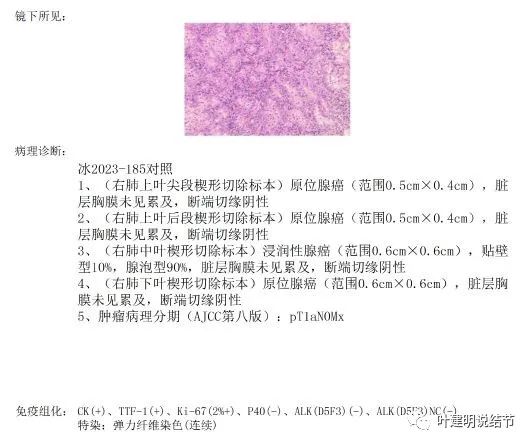

下面是术后病理结果:

确实如术前判断,上叶尖段病灶2、后段病灶6与下叶灶8是原位腺癌,中叶病灶9是浸润性腺癌,贴壁占10%,腺泡型占90%。切缘均阴性。